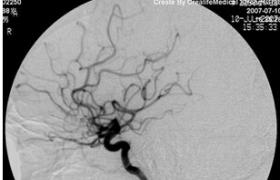

脑血管造影